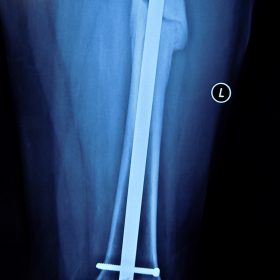

Κατάγματα Μηριαίου ή Κνήμης

Τα κατάγματα της Διάφυσης των οστών της κνήμης και του Μηριαίου οστού στη σύγχρονη ΟΡΘΡΟΠΑΙΔΙΚΗ αντιμετωπίζονται με ΕΝΔΟΜΥΕΛΙΚΗ ΗΛΩΣΗ.

Δύο τομές 3 εκατοστών και 1 εκατοστού αντιστοίχως για την εισαγωγή και το κλείδωμα του ήλου μέσα στο οστό. Η μέθοδος είναι κλειστή,σχεδόν αναίμακτη,διάρκειας 60 λεπτών,με τη βοήθεια C-ARM (τηλεόρασης).

Στον ασθενή παρέχεται οπτικό υλικό (όλα τα χειρουργικά στάδια) σε CD ή Στικάκι,λόγω της δυνατότητας καταγραφής του χειρουργείου από το C-ARM Ο ασθενής περπατάει άμεσα μετεγχειρητικά στις 5 ώρες μετά την επέμβαση και εξέρχεται από το νοσοκομείο σε 1 -2 ημέρες.